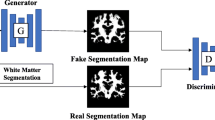

White matter hyperintensities (WMH) are typically segmented using MRI because WMH are hardly visible on 18F-FDG PET/CT. This retrospective study was conducted to segment WMH and estimate their volumes from 18F-FDG PET with a generative adversarial network (WhyperGAN).

We selected patients whose interval between MRI and FDG PET/CT scans was within 3 months, from January 2017 to December 2018, and classified them into mild, moderate, and severe groups by following the semiquantitative rating method of Fazekas. For each group, 50 patients were selected, and of them, we randomly selected 35 patients for training and 15 for testing. WMH were automatically segmented from FLAIR MRI with manual adjustment. Patches of WMH were extracted from 18F-FDG PET and segmented MRI. WhyperGAN was compared with H-DenseUnet, a deep learning method widely used for segmentation tasks, for segmentation performance based on the dice similarity coefficient (DSC), recall, and average volume differences (AVD). For volume estimation, the predicted WMH volumes from PET were compared with ground truth volumes.

Although limited by visual analysis, the WhyperGAN based can be used to automatically segment and estimate volumes of WMH from 18F-FDG PET/CT. This would increase the usefulness of 18F-FDG PET/CT for the evaluation of WMH in patients with cognitive impairment.

Oh KT, Lee S, Lee H, Yun M, Yoo SK. Semantic segmentation of white matter in FDG-PET using generative adversarial network. J Digit Imaging. 2020. https://doi.org/10.1007/s10278-020-00321-5.